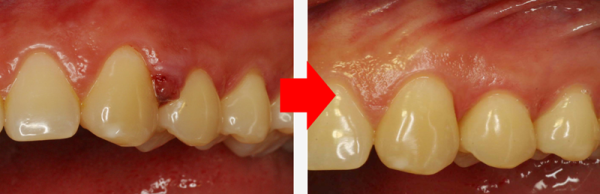

물방울레이저로 치아와 잇몸 사이의 틈에 에너지를 주사해 그 어떤 절개나 봉합 없이 제거를 도와드립니다.

치료 전과 치료 후는 이렇게 달라집니다.